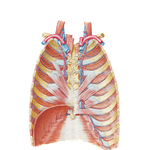

• Anterior Thoracic Wall: Internal View

196. Anterior Thoracic Wall: Internal View